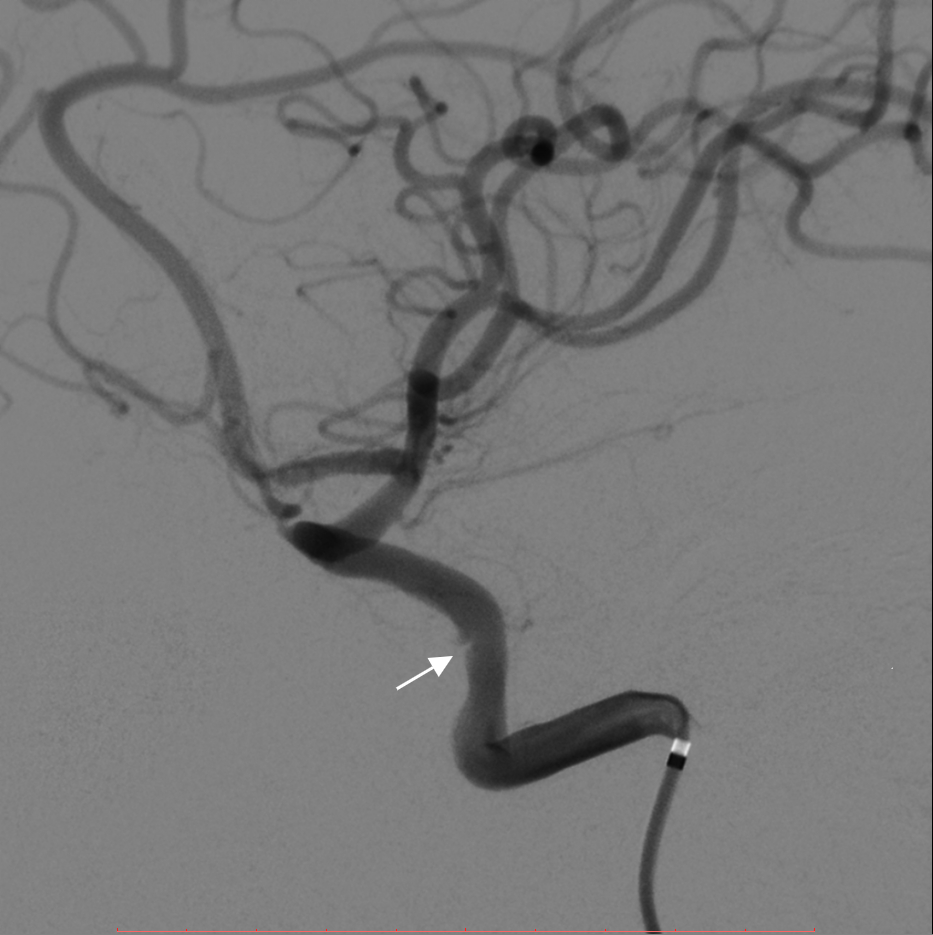

在全麻下,患者取仰卧位,通过鼻腔填塞肾上腺素脑棉片收缩黏膜,聚维酮碘(povidone iodine, PVP-I)溶液进行鼻腔消毒和手术铺巾。利用神经外科手术导航系统确定肿瘤位置及方向,在神经内镜下磨除蝶窦前壁及鞍底骨窗,见肿瘤突入蝶窦腔。肿瘤质地坚韧,血供丰富,颜色黄红。镜下使用超声刀(cavitron ultrasonic surgical aspirator, CUSA)逐步切除肿瘤。术中海绵间窦出血明显,给予止血材料速即纱、流体明胶、明胶海绵止血。止血确切后,多普勒探及两侧颈内动脉。术中见鞍隔塌陷,提示视神经压迫解除,未见明显脑脊液漏。肿瘤突入两侧海绵窦,包绕双侧颈内动脉。在吸除左侧颈内动脉斜坡段肿瘤时,突发颈内动脉破裂,出血量大。立即给予捆绑明胶海绵加压填塞压迫止血,同时通知复合手术室,准备全脑血管造影及左侧颈内动脉覆膜支架植入术。密切监测生命体征及出血量,压迫后出血缓解,继续填塞后未见活动性出血,予人工脑膜修复鞍底,明胶海绵填塞和胶水固定,蝶窦内填塞明胶海绵支撑鞍底,碘仿纱条一根填塞鼻腔,术中麻醉满意,出血较多,输注悬浮红细胞400 mL,标本送病理,送复合手术室。患者平卧数字减影血管造影(digital subtraction angiography, DSA)床,常规消毒铺巾。经右侧股动脉穿刺,行全脑血管造影见左侧颈内动脉破裂孔段侧壁充盈缺损,可见少量造影剂外渗(见图 2),考虑为出血点。在导丝引导下,在出血点处逐步释放Willis覆膜支架4.5 mm×16 mm一枚,覆盖出血点。造影复查显示颈内动脉破裂孔段充盈缺损消失,未见造影剂外渗,支架帖壁良好,动脉通畅,闭合器闭合右侧股动脉穿刺点。手术过程顺利,术中生命体征平稳。

| 左侧颈内动脉破裂孔段侧壁可见少量造影剂外渗(白色箭头) 图 2 患者术中全脑血管造影(DSA) |